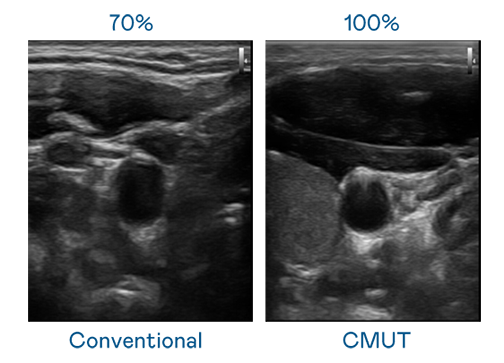

CMUT 技术是一种用电容式微机电元件来产生超音波讯号的技术。与传统 PZT 压电式技术相比,CMUT 频宽增加 30%,更宽频的超音波讯号让影像解析度大幅提升,是实现高影像品质医疗超音波扫描、促进精准医疗发展的关键技术。

大频宽带来超清晰影像

超音波影像的解析度高低,首先取决于探头能发出的讯号频宽。新官人我耍迅雷下载mp4 CMUT 可提供高清晰的超音波讯号,提供高频宽、高灵敏度、影像纹理细节更高的超音波影像,协助医护人员缩短影像判读时间及利用精准的医疗影像进行诊断。